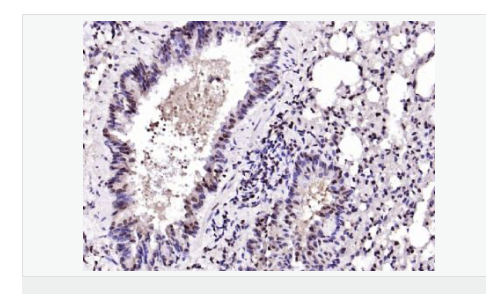

| 研究領域 | 腫瘤 細胞生物 神經生物學 細胞周期蛋白 |

| 產品應用 | ELISA=1:5000-10000 IHC-P=1:100-500 IHC-F=1:100-500 IF=1:100-500 (石蠟切片需做抗原修復) not yet tested in other applications. optimal dilutions/concentrations should be determined by the end user. |

| 產品介紹 | The protein encoded by this gene is a member of the BTG/Tob family. This family has structurally related proteins that appear to have antiproliferative properties. This encoded protein might play a role in neurogenesis in the central nervous system. Two transcript variants encoding different isoforms have been found for this gene. [provided by RefSeq, Aug 2008]. Function: Overexpression impairs serum-induced cell cycle progression from the G0/G1 to S phase. Subunit: Interacts with KCNMA1 tetramer. There are probably 4 molecules of KCMNB1 per KCNMA1 tetramer. Subcellular Location: Membrane; Multi-pass membrane protein. Tissue Specificity: Abundantly expressed in smooth muscle. Low levels of expression in most other tissues. Within the brain, relatively high levels found in hippocampus and corpus callosum. Similarity: Belongs to the KCNMB (TC 8.A.14.1) family. KCNMB1 subfamily. SWISS: Q14201 Gene ID: 10950 Database links: Important Note: This product as supplied is intended for research use only, not for use in human, therapeutic or diagnostic applications |